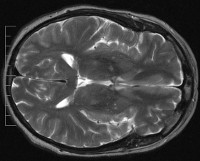

Основными методами являются компьютерная томография, электроэнцефалография и транскраниальная допплерография. При КТ головного мозга, признаки потребления жидкости или отек, органические очаги повреждения обнаружены. ЭЭГ определяет динамику внутримозговой импульсной проводимости - обычно пострескулярная энцефалопатия приводит к ослаблению. С помощью TD вы можете оценить уровень кровоснабжения головного мозга и функции сосудистого аппарата. Более информативной альтернативой исследованию является изотопная ангиография.